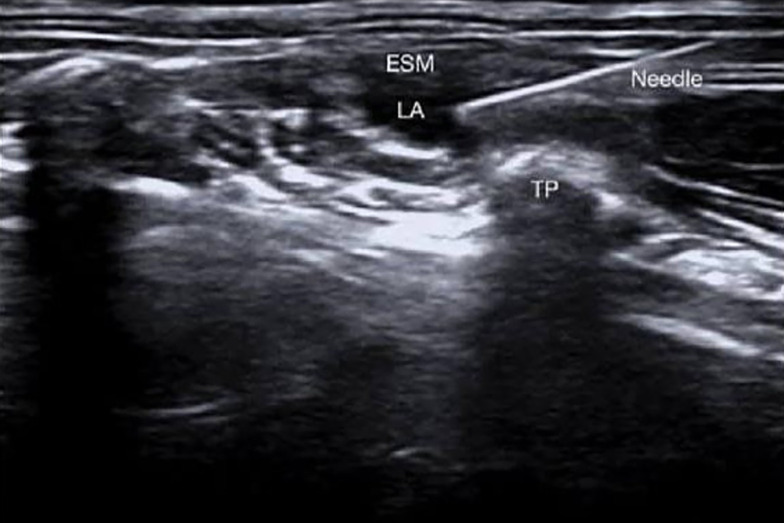

Methods: This randomized, controlled, single-blinded clinical study was conducted on 50 individuals aged 20 to 60 years, of both genders, with American Society of Anesthesiology (ASA) grade I and II physical status, undergoing LC. Subjects were allocated using a computer-generated randomization table into two equal groups: Group A received an ultrasound (US)-guided ESP block, and group B received a US-guided OSTAP block.

Abstract Image